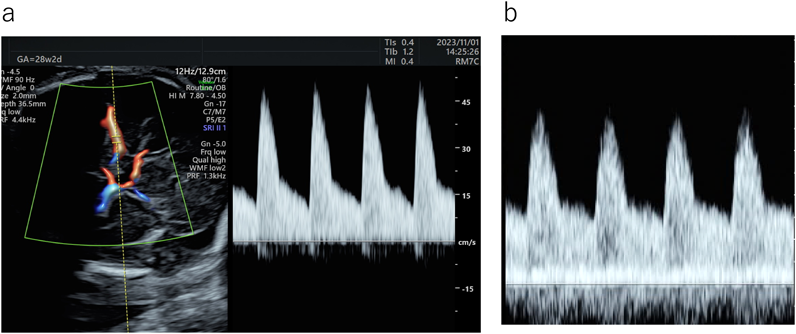

6. 房室弁流入波形(E/A比)

拡張能の指標として用いられる.心室流入血流波形であるE波(拡張早期波:心室弛緩に伴う受動血流)とA波(心房収縮波:心房収縮に伴う拡張後期の血流)の比である.成人では,E波がA波よりも高いが,胎児ではE波よりもA波のほうが高い.これは胎児では拡張能が低い(弛緩能が低く,コンプライアンスも低い)ことによるとされ,流入血流における心房収縮の役割がより大きいことを示す.妊娠週数に伴いE/A比も増加していく(Fig. 6).胎児のE/A比は妊娠初期で約0.5,中期で約0.8と増加する16–20).重度の心不全ではE波とA波は融合し単峰性となるとされる9, 21).なお頻脈でもE波とA波を区別しにくくなる.

Pediatric Cardiology and Cardiac Surgery 40(4): 250-259 (2024)

Fig. 6 右室流入血流波形(E/A比)

E/A比は胎児では<1であるが,妊娠週数に伴い増加していく.a:妊娠19週E/A:0.63.b:妊娠28週E/A:0.71.c:妊娠34週E/A:0.77.